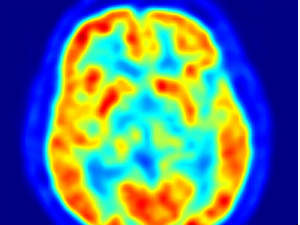

बड़ा खुलासा: जानिए क्यों सठियाते है लोग

इसमें पाया गया कि इनमें बुद्धिमता का आनुवांशिक तत्व होता है। लेकिन यह जीवनपर्यंत कैसे बदलता है यह पता नहीं था। ब्रिटेन के एडिनबर्ग विश्वविद्यालय में किये गये नवीनतम शोध में पता चला है कि जीन और परिवेश के अनसार व्यक्ति की बुद्धि उम्र के साथ कैसे बदलती है। लाइवसाइंस पत्रिका की खबर के अनुसार शोधकर्ताओं के दल के प्रमुख इयान डियरी ने कहा कि ये परिणाम बताते हैं कि उम्र के बढ़ते जाने के साथ बुद्विमता पर परिवेश और जीन का असर पड़ता है।

उन्होंने बताया कि शोधकर्ताओं ने स्काटलैंड के 1,940 लोगों के बुद्वि के स्तर की 11 वर्ष की उम्र में जांच की थी। हाल ही में उनकी बुद्धि के स्तर की जांच तब की गयी जब उनकी उम्र 65 से 79 वर्ष हो गयी। शोधकर्ताओं ने कहा कि इन व्यक्तियों के जीन का उनकी बुद्धि पर प्रभाव पड़ा था लेकिन बढते उम्र के साथ उनके परिवेश के अनुसार भी उनकी बुद्धिमता में बदलाव आया। शोधकर्ताओं के अनुसार बुद्धि के स्तर का 25 प्रतिशत जीन के अनुसार बदलता है वहीं बाकी परिवेश के अनुसार बदलता है। परिवेश के अनुसार कुछ लोगों की बुद्धि का स्तर बेहतर होता है वहीं कुछ का कम हो जाता है।